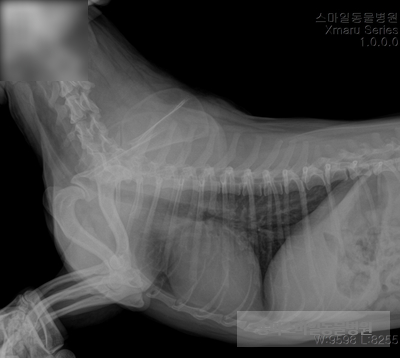

수액처치후 “ㄹ” 긴급수술 하였습니다.

수술은 안전하게 마무리되었습니다.

자궁 내부는 곪아 있었습니다.

중성화 수술의 경우 당일 퇴원 가능하지만, 자궁 축농증의 경우 교정치료가 필요하기 때문에 입원하게 되며, 입원 일수는 자녀의 상태에 따라 달라집니다.

‘ㄹ’은 교정치료 후 식욕, 활력이 높아져 건강하게 퇴원하였습니다.

며칠 후 봉합사 제거로 치료는 끝났습니다.